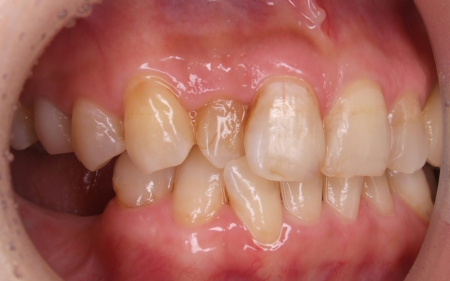

拝見したところ、歯と歯が並ぶ土台の骨「歯槽基底」の大きさの不調和により歯並びがガタガタになる「叢生(そうせい)」が全体的に生じており、また上下の前歯の重なりが深いため下の歯が見えない「過蓋咬合(かがいこうごう)」も認められました。

下の奥歯5本(右第2小臼歯/5番、左右第1大臼歯/6番、左右第2大臼歯/7番)が欠損したまま長く放置されていたことが原因で、噛み合う歯がなかった左上の奥歯(第1大臼歯)は本来の位置より下に伸びる「挺出(ていしゅつ)」が起き、左下の歯2本(第1小臼歯/4番、第2小臼歯)も内側に倒れたことで、下前歯の叢生が悪化したと考えられます。

さらに左上の歯(第1小臼歯)の欠損部位は両隣の歯2本(犬歯/3番、第2小臼歯)を土台に人工歯を橋渡しにする被せ物「ブリッジ」が装着されており、お口を開けたときに銀歯が目立つことに加えて、歯の色が全体的に黄ばんでいるため見た目が良くない状態でした。